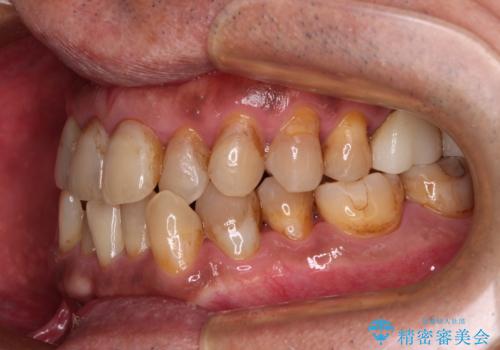

今からでも綺麗な歯並びを手に入れたい 40代男性のワイヤー矯正

- 前歯のクロスバイトを気にして来院された患者様です。

40代男性で、インプラント補綴治療も経験されている方で、矯正治療をしても良いのかと悩んでいらっしゃいました。

下顎骨の左右のずれがあり、下顎全体が前方に出ている状態であったので、無理をせずにワイヤー装置にて矯正治療を行うこととしました。

クロスバイト改善には難儀しましたが、咬みやすく、笑ったときに清潔感ある口元に仕上げることができました。